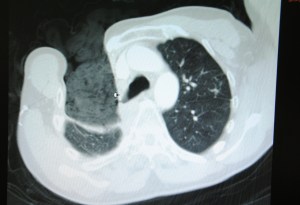

Over the continuing course of his treatment, a large opening on the anterior chest was created surgically.  Due to the extent of necrotic tissue, this required the removal of anterior sections of ribs #2, 3, 4 and 5, leaving the patient with a very large open cavity, as seen in CT slices (pulmonary and tissue windows).

BPF CT1

packing material can be seen in the right chest cavity.

tissue window showing extent of wound

This large cavity was left open for a period of around two years, while infected material was debrided and evacuated, and aggressive wound management was continued.  At the time of his presentation to the operating room, the wound bed is dry and pink with a small amount of slough.  An opening to the bronchus is visible (with bubbling on respiration at the site of the wound). The wound measures approximately  6 cm X 4 cm.  As seen from the CT images above, the wound was also several centimeters in depth.